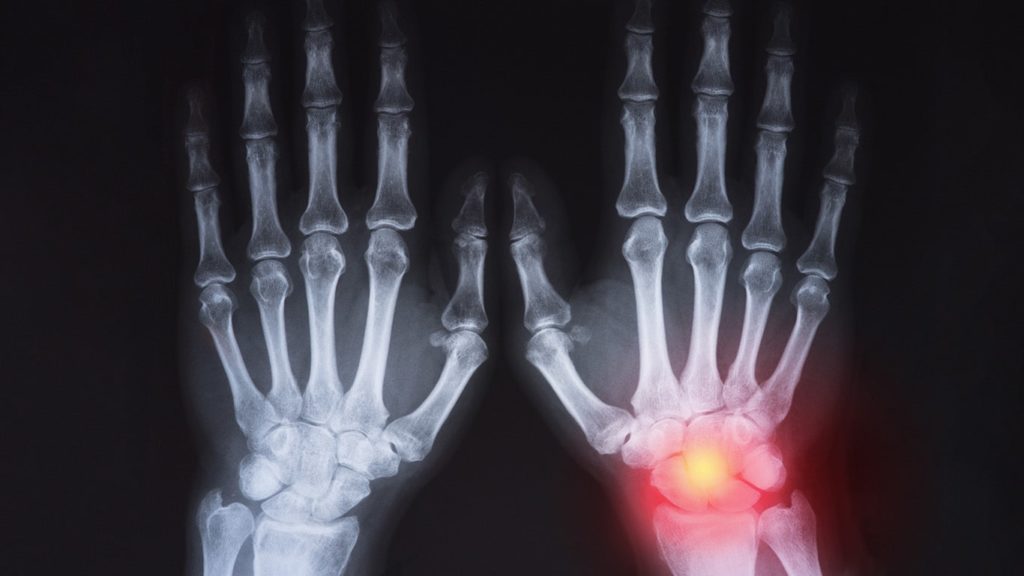

Today, with X-Ray technology, we can diagnose all types of cancer, broken bones, and other problems. We have already covered different types of X-Rays. In this discussion, let’s take a deep look into its advantages and disadvantages.

The most obvious advantage of using X-Rays is to look inside the body without having the need to perform surgery. At the time of its discovery, it was used by doctors to look for bullets inside the body and fractures in the bones. Following are some other advantages of using X-Ray.

4. Diagnose tumors

The X-ray procedure is usually painless, making it an ideal option to diagnose tumors. Tumors are nothing but an abnormal mass of tissue that can sometimes become cancerous. And that’s where the problems begin. X-rays help to detect what occurs inside the body and identify if it’s cancerous.

This increases the chances of successful treatment. When diseases are detected at an early stage, they can be comparatively managed well. In the process, reducing the patient’s distress and avoiding the financial burden of expensive treatments.

In the X-ray procedure, the radiation is absorbed by the body parts in varying degrees. The dense bone absorbs more radiation, and hence appears white in the radiographic images. Whereas, the soft tissues absorb less radiation and appear gray. The black area that you see in the image is nothing but the air. The calcium in bones absorbs more radiation and in the worst-case scenario leads to fracture and growth arrest.